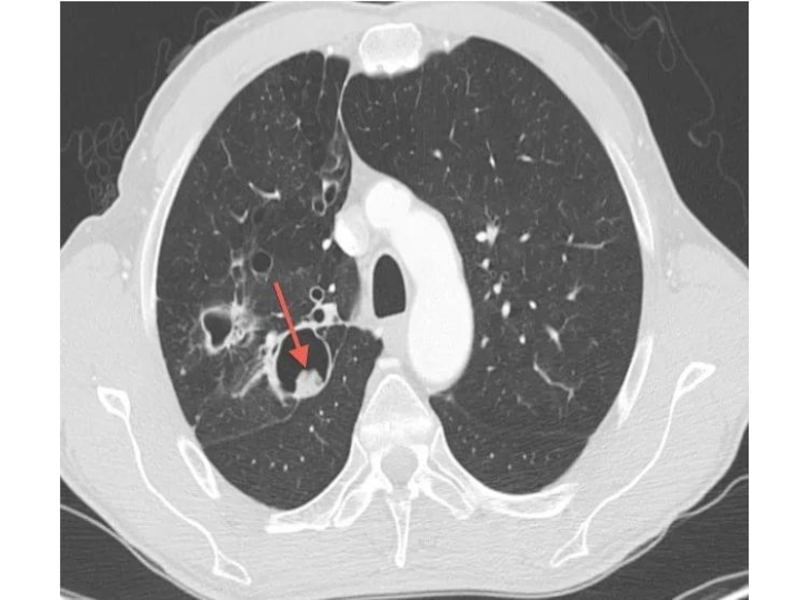

Слайд 52Абсцедирующая пневмония

Абсцесс выглядит как кольцевидная тень с уровнем жидкости.

Абсцедирующая пневмонияАбсцесс выглядит как кольцевидная тень с уровнем жидкости.